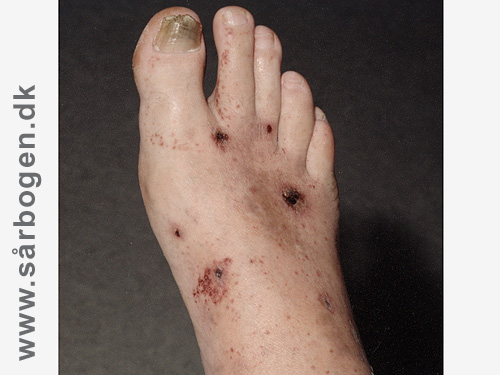

Zoom

Buerger